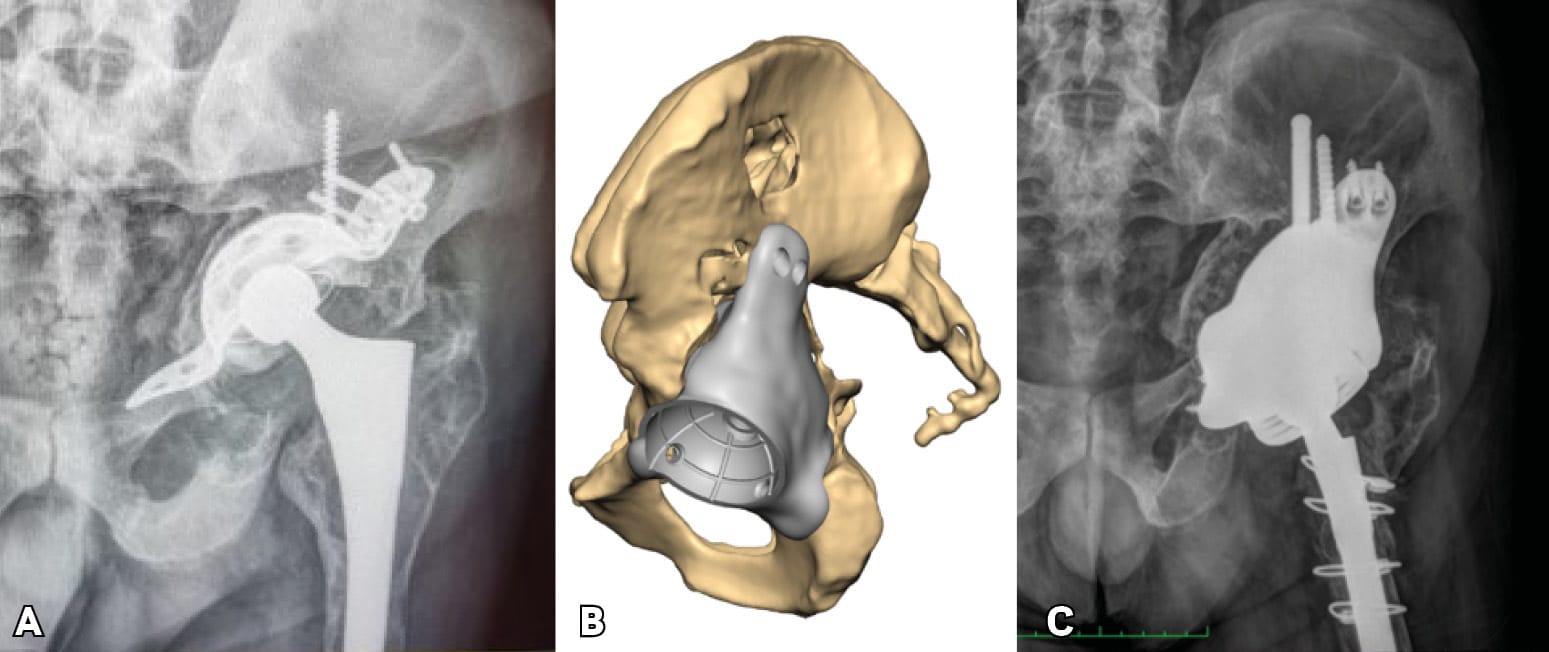

Severe post-operative defects. Principles of management and outcomes of specific patterns are not clearly reported in the literature. Based on the Sen clacification,[1] Sen RK, Mukhopadhyay R, Pattanshetti V, Saini G, Tripathy SK, Sethy SS, Sharma SK. A New Classification System for Acetabular Bone Defect Evaluation in Posttraumatic Acetabular Nonunion and Malunion. Indian J Orthop. 2022 Jun 27;56(9):1601-1612 types 1, 2, 3-A and 5 can be treated with surgical techniques used in revision THA surgery. For severe defects (such as 3-B, 4-A and 4-B), the restoration of hip center of rotation, cup offset, inclination and anterversion and hip stability can be achived only with custom-made implants (Figures 3 and 4).

Triflange and tumour like custom made acetabular impants. Modern technology allows the production of personalised implants for special conditions. These type of implants are custom made, porous coated titanium implants and are considered the last therapeutic salvage option, before excisional arthroplasty, for severe acetabular defects and PD. The implants are designed and manufactured based on pelvic models created by thin-slice pelvic 3-D CT-scans with metal subtraction software (Figures 7 and 8). Early and mid-term outcomes are encouraging but premium cost and length of production time limit their use.[20], DeBoer DK, Christie MJ, Brinson MF, Morrison JC. Revision total hip arthroplasty for pelvic discontinuity. J Bone Joint Surg Am. 2007; 89(4):870-876.[21], Taunton MJ, Ferhing TK, Edwards P, Bersasek T, Holt GE, Christie MJ. Pelvic discontinuity treated with custom triflange component: a reliable option. Clin Orthop Relat res. 2012; 470(2):428-434.[22] Zhang Y, Gao Z, Zhang B, Du Y, Ma H, Tang Y, Liu Y, Zhou Y. The application of custom-made 3D-printed titanium augments designed through surgical simulation for severe bone defects in complex revision total hip arthroplasty. J Orthop Traumatol. 2022; 6:23(1):37.

Concerns for the use of custom made implants are related to the accuracy of the image based technique used for their production, the accuracy of the implant 3D fitting and implantation, the appropriate surgical approach and exposure and the manufacturing and biology of the implant-bone interface.[23], Hothi H, Henckel J, Bergiers S, Di Laura A, Schlueter-Brust K, Hart A. The analysis of defects in custom 3D-printed acetabular cups: A comparative study of commercially available implants from six manufacturers. J Orthop Res. 2023; 41(7):1505-1516.[24], Di Laura A, Henckel J, Wescott R, Hothi H, Hart AJ. The effect of metal artefact on the design of custom 3D printed acetabular implants. 3D Print Med. 2020; 26:6(1):23. [25] Gruber MS, Jesenko M, Burghuber J, Hochreiter J, Ritschl P, Ortmaier R. Functional and radiological outcomes after treatment with custom-made acetabular components in patients with Paprosky type 3 acetabular defects: short-term results. BMC Musculoskelet Disord. 2020; 10:21(1):835.